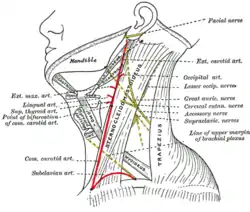

The nerves of the scalp, face, and side of neck. Side of neck, showing chief surface markings.

Side of neck, showing chief surface markings. Lateral head anatomy detail

Lateral head anatomy detail